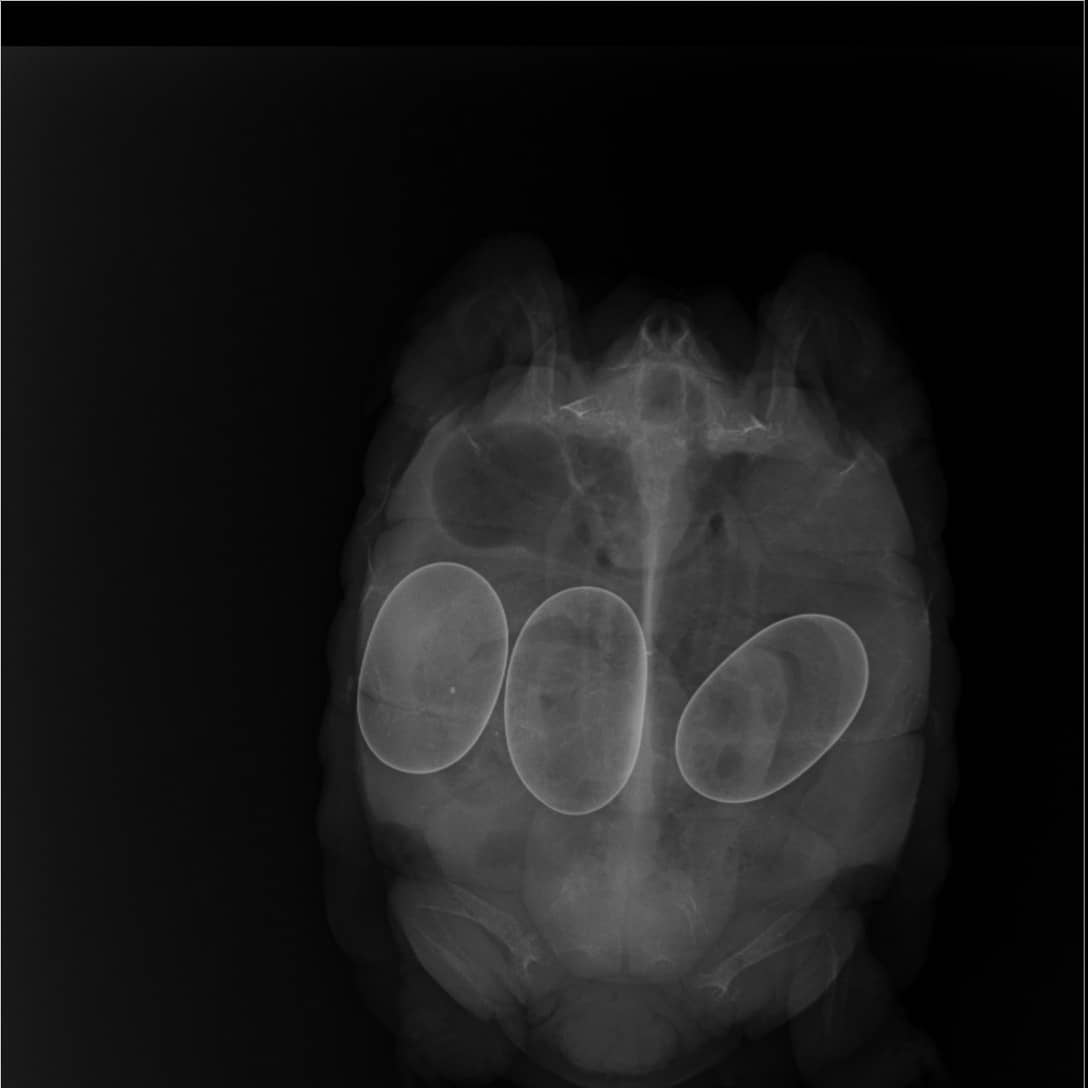

The reptile's initial medical examination at the Thane SPCA and the x-ray reports reveals presence of three eggs. (3/N)

The tortoise is currently receiving daily treatment by Dr Archana Bapat. The reptile's latest medical examination reveals that it has reached the advanced stage of Metabolic Bone Disease and has very poor chances of survival. (4/N)

Its shell has turned rubber-soft due to prolonged lack of UVB exposure & required dietary supplements.

When tortoise is suffering from MBD its body starts absorbing calcium required for normal metabolic & hormonal funct. from shell, thereby causing excessive softening. (5/N)